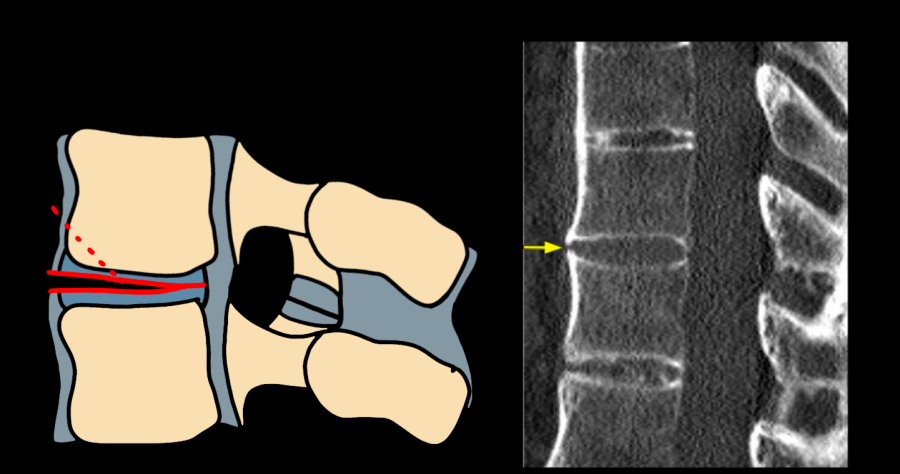

AO Type B1/B2 flexion-distraction Chance fracture — diagram and CT showing posterior tension band disruption with anterior distraction

Type B1/B2 — flexion-distraction (Chance fracture equivalent); posterior tension band failure